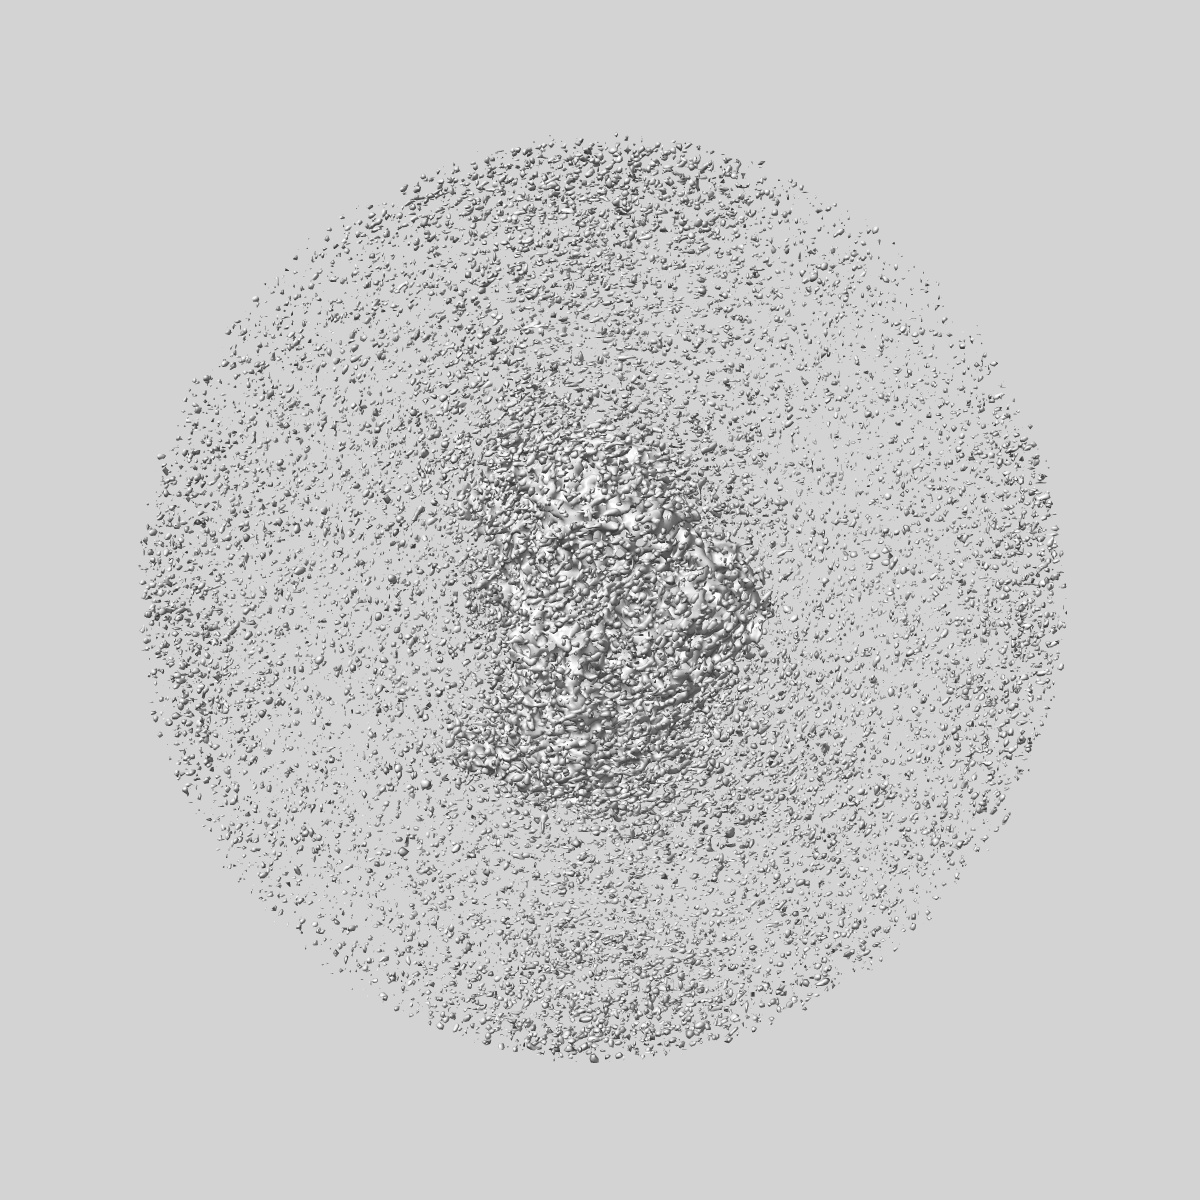

Cryo-EM structure of TAP binding protein related (TAPBPR) in complex with HLA-A*02:01 bound to a suboptimal peptide.

Single-particle3.0 Å

Sample: Complex of peptide loaded HLA-A*02:01/beta-2-microglobulin in complex with human TAPBPR.

CryoEM structure of an MHC-I/TAPBPR peptide-bound intermediate reveals the mechanism of antigen proofreading.